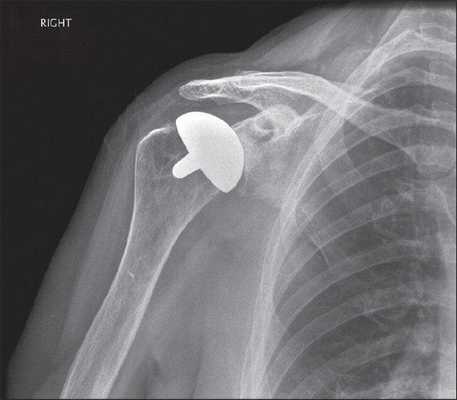

• Гемиартропластика плечевого сустава: имплант замещает только головку плечевой кости, суставная впадина лопатки сохраняется:

о Иногда используется на протяжении нескольких десятков лет:

- Первично использовалась при разрушении головки плечевой кости (остеонекроз, тяжелый осколочный перелом) без артритических изменений

о Ножка и головка плечевой кости металлические:

- С цементной или бесцементной фиксацией

• Гемиартропластика плечевого сустава: имплант замещает только головку плечевой кости, суставная впадина лопатки сохраняется